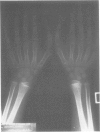

This report describes a family with bilateral non-opposable triphalangeal thumb, bringing to two the number of families with this autosomal dominant disorder.